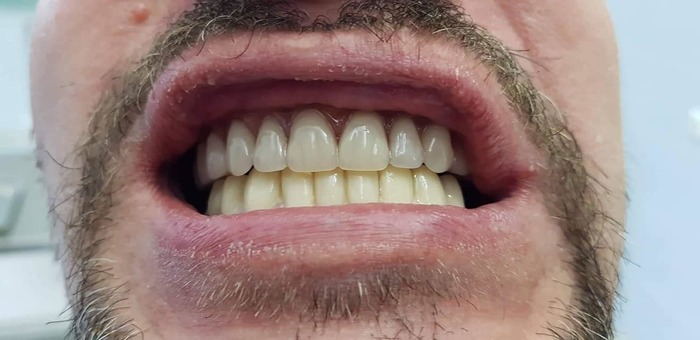

А дальше, 3 ноября, за 3 часа времени со мной сделали вот это:

Заметили на последней фотке, какие у меня нижние зубы?

Расскажу маленькую предысторию и вообще про Георгия. Он по образованию челюстно-лицевой хирург, работал в Питере, несколько лет обучался и работал в Париже, с примерно 2003 года практикует одноэтапную имплантацию. Два года назад вернулся в родной город - Батуми - и сделал там клинику. Клиника чисто семейная - я когда понял, что на площадке подъезда одна дверь - это клиника, а вторая - это их квартира,  это все в мансарде четырехэтажного дома и имеет общую террасу, то понял, что мои вопросы в переписке - до скольки они работают и работают ли в выходные - ну, слегка бессмысленны. Например, я прилетел в Батуми в 3 часа дня, в 4 был в гостинице, в 6 за мной зашла Хатуна - супруга Георгия и тоже стоматолог - и показала мне, где клиника и они с зубным техником - Гочей - сразу сняли слепки челюстей, прикинули, какой должен быть прикус, и решили, что сначала надо поправить нижние зубы, чтобы от них уже верхнюю челюсть строить. Собственно, с 30 октября по 2 ноября мне сделали нижние зубы и одели на них коронки. Именно они сейчас на мне и их вы видите на фото. Опять же, замечу, что параллельно они занимались семейной парой из Красноярска, по моему, и парой из Израиля. У красноярцев лечилась жена, у израильтян - муж. В файсбуке Георгия в записях между 30 октября и 6 ноября - мы трое, на фотографиях и видеороликах.

А это - мои новые зубы:

Буду учиться по новой улыбаться, есть и разговаривать - с кем из родственников говорил - отмечают, что с шипящими у меня некоторые проблемы еще есть; но, думаю, с разговорной практикой все наладится.